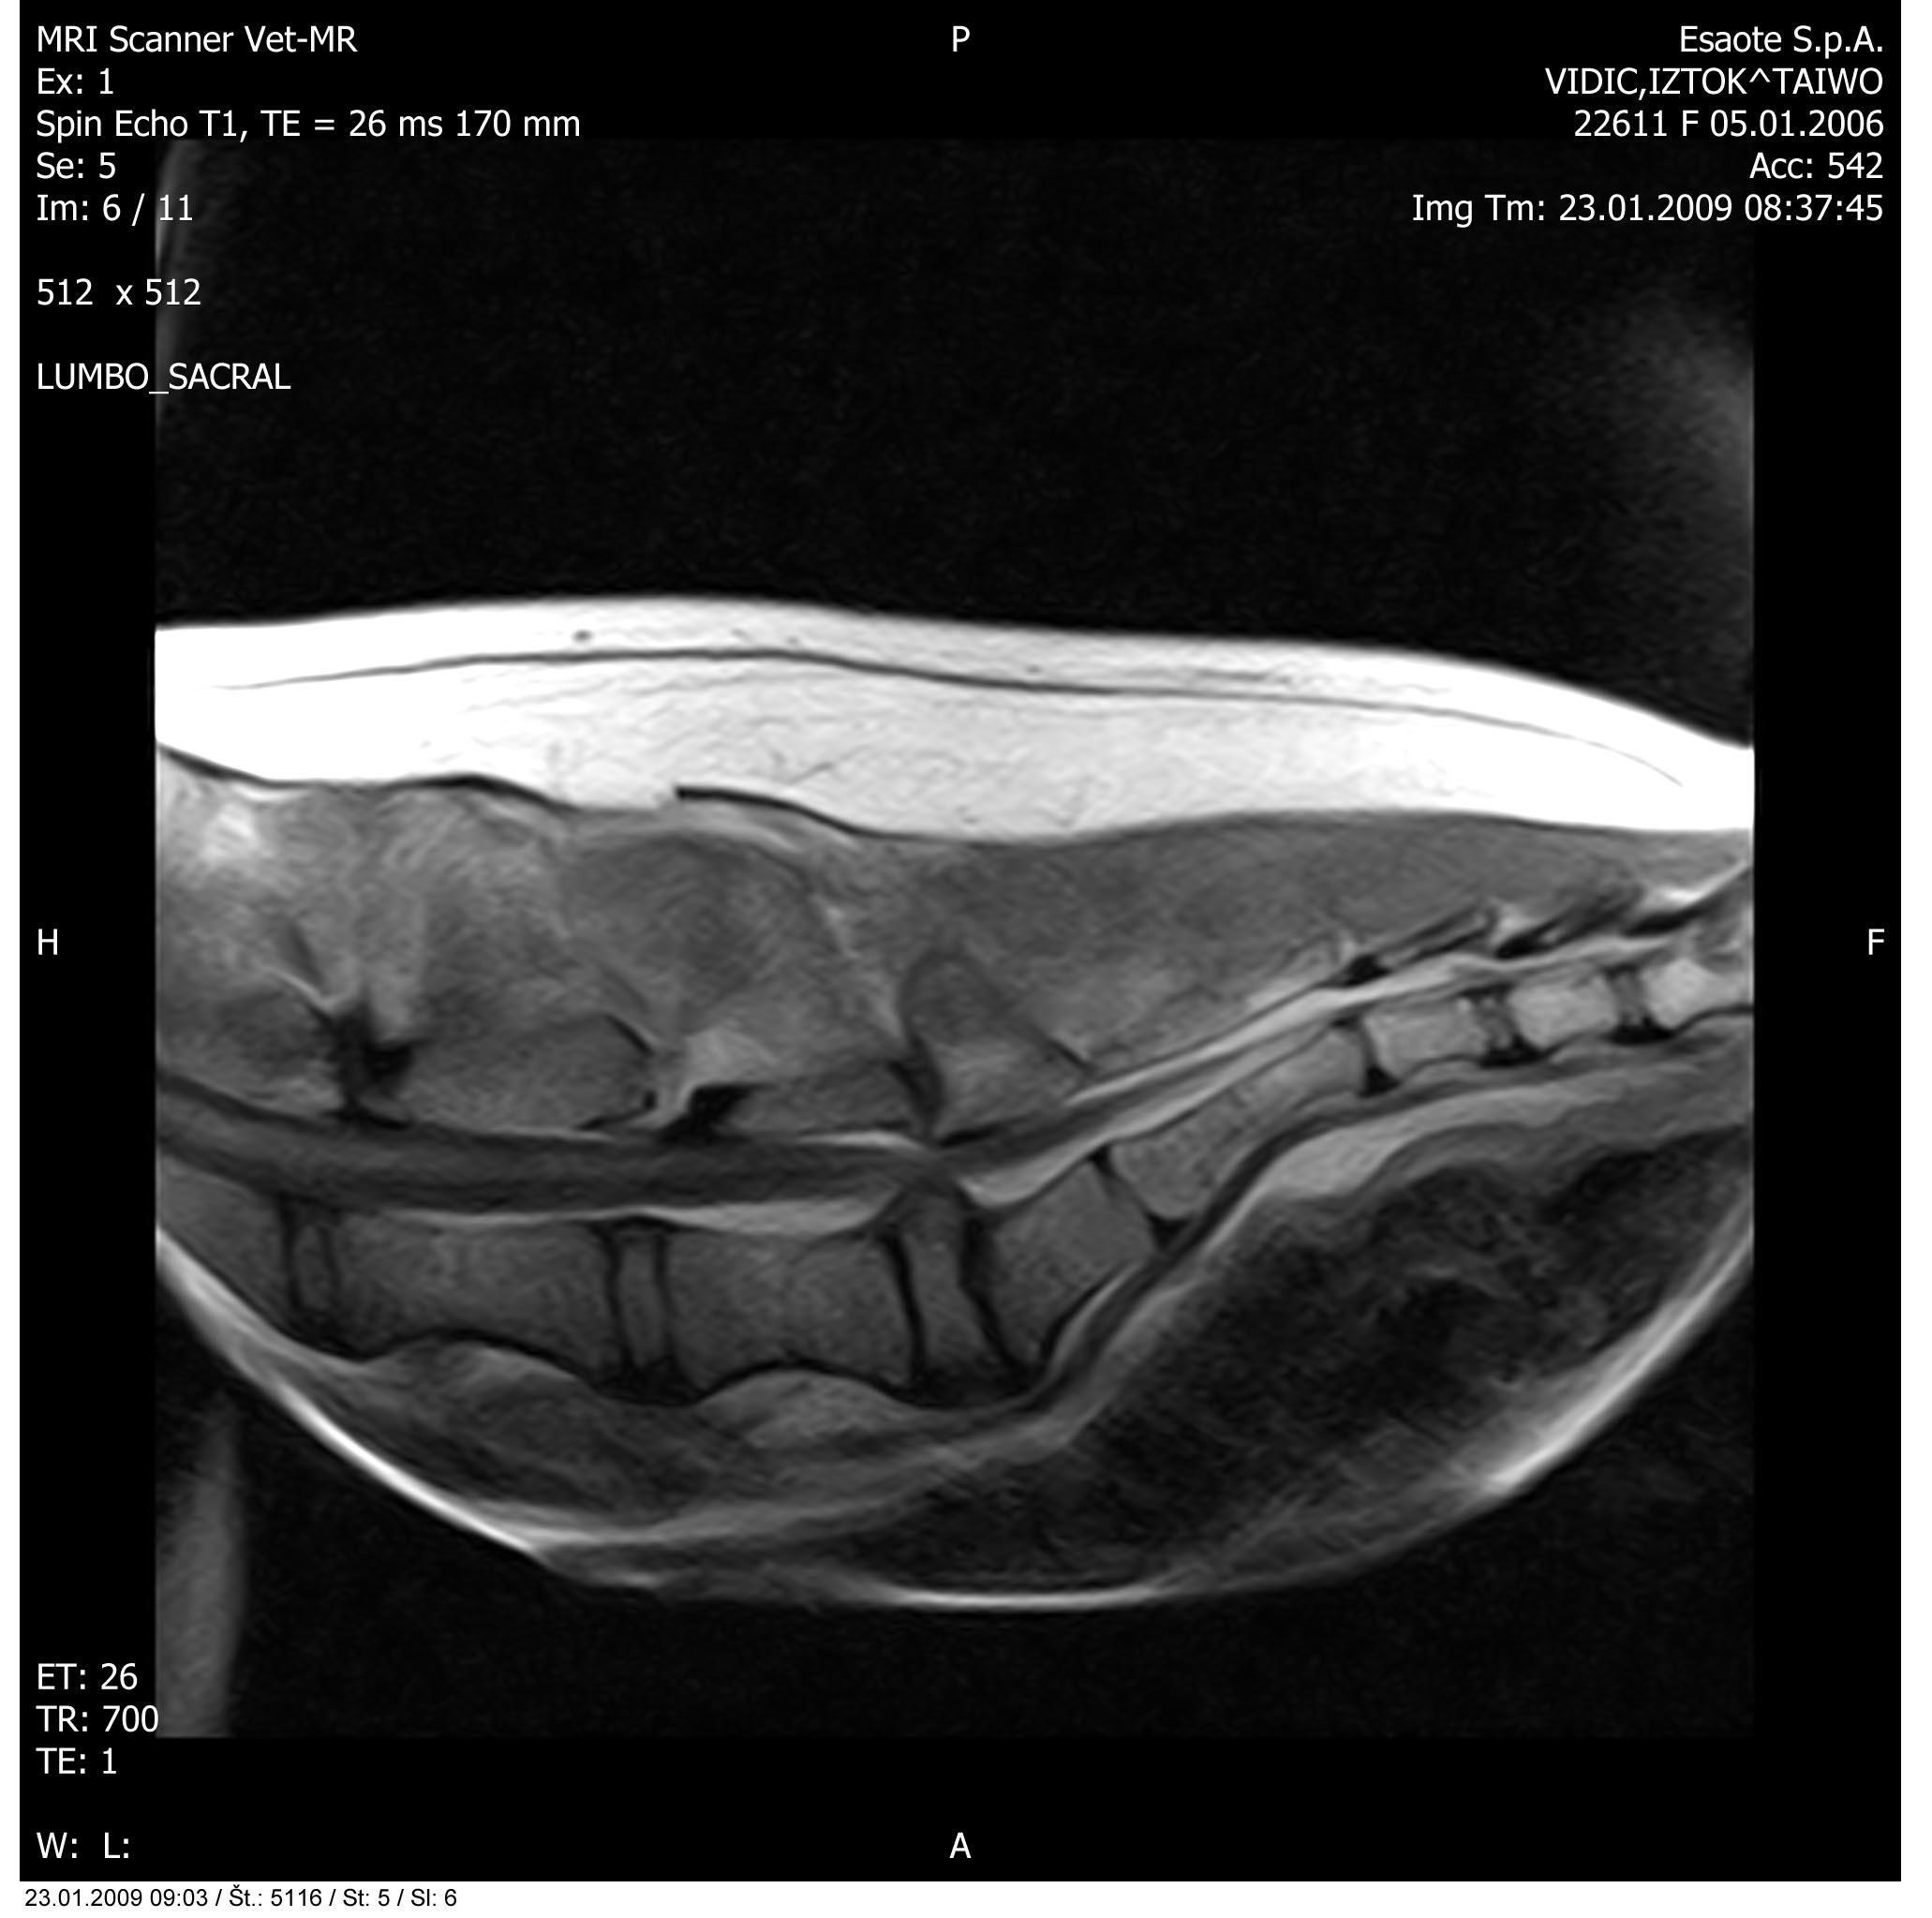

Slika: Primer zdrsa medvretenčnega diska v ledvenokrižnem področju

Slika: Primer vnetega medvretenčnega diska

Magnetna resonanca je torej diagnostična metoda izbora pri ugotavljanju patoloških dogajanj v mehkih tkivih glave in hrbtenice. O leziji pri MR govorimo o vsakem področju, kjer je signal drugačen kot običajno. Na podlagi ocene slik v vseh treh ravninah natančno določimo lokacijo, obseg in vpliv spremenjenih tkiv na okolna tkiva.

Zanima nas število lezij, njihova oblika, robovi, vraščenost, ugotavljamo prirojene ali pridobljene anomalije (na primer hidrocefalus, siringomielija in drugo), potrdimo tipe lezij: degenerativne (na primer starostna atrofija, degenerativna mielopatija, bolezni medvretenčnih diskov in drugo), tumorozne (na primer meningiomi, gliomi, metastaze in drugo), vnetne (na primer meningoencefalitis, diskospondilitis in drugo), žilne (infarkti, poškodbe, embolija diska in drugo) ter druge.